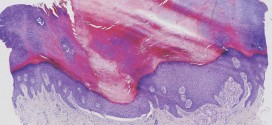

La epidermólisis ampollosa. Enfermedad hereditaria que se caracteriza por la formación de ampollas claras, ovales y hemorrágicas; suelen estar causadas por golpes, exceso de presión o traumatismos. Aparecen en zonas expuestas como las manos, los pies, las rodillas y los codos de varones. El tratamiento consiste en corregir los trastornos hidroelectrolíticos y proteicos así como prevenir las infecciones. Especialmente si no …

La enfermedad de darier (queratosis folicular). Dermatosis de tipo hereditario que se transmite de forma autosómica dominante cuya causa es una alteración de la queratinización. Sin embargo existe un elevado número de casos que ocurren de forma espontánea sin que tengan ningún antecedente familiar. Que causa pequeñas erupciones tipo costra que por confluencia origina grandes placas verrucosas de color gris …

La psoriasis. Es una enfermedad muy común que afecta entre el 1y 2% de la población mundial. Se caracteriza por la aparición de pápulas eritemato-escamosas y placas recubiertas por gruesas escamas nacaradas. Resumiendo: En el 10% de los casos el psoriasis se asocia a artritis (otra que no ha respetado a la madre naturaleza). El comienzo puede ocurrir a cualquier …

La hiperqueratosis. La hiperqueratosis es un engrosamiento de la capa externa de la piel. Esta capa externa contiene una proteína resistente y protectora, llamada queratina. Hipertrofia de la capa cornea de la piel. Aumento congénito o adquirido de la capa córnea de la epidermis. Este engrosamiento de la piel es a menudo parte de la protección normal de la piel …